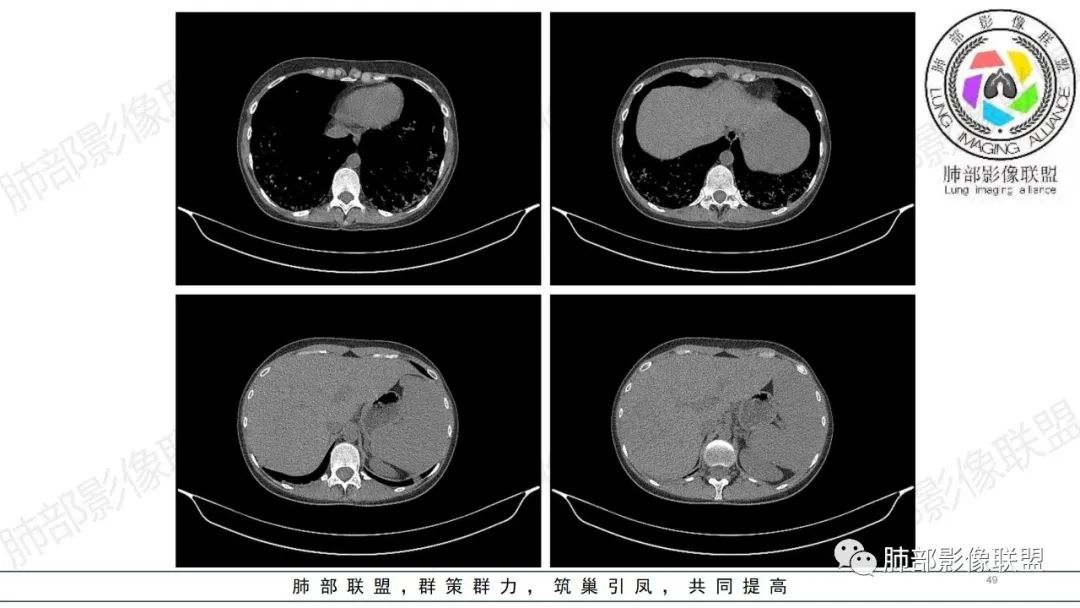

【病例】肺部弥漫大B淋巴瘤病例思考及启示

肺内气腔磨玻璃结节,肝脾肿大,治疗后间质改变,弥漫大B可能

34岁女性患者,“哮喘”病史30年,近期有可疑刺激性气体吸入史;因乏力半年,咳嗽、憋气、发热4天就诊;6.1CT提示双肺广泛毛玻璃影及粟粒样结节,胸膜下闲置及血管周闲置,可见树丫征,部分小叶间隔增厚。考虑:1.过敏性肺泡炎,有可疑刺激气体接触史,胸膜下闲置,广泛毛玻璃影,地图样分布,粟粒结节边界模糊,支持过敏性肺泡炎,但糖皮激素治疗效果不佳,且动态复查血常规血红蛋白进行性降低,过敏性肺泡炎 不符合;2.肺含铁血黄素沉积症:患者30“哮喘”病史,可能为肺含铁症状,肺部CT提示双肺弥漫毛玻璃影及粟粒结节影,中下肺明显,肺底部分小叶间隔增厚,近期咳嗽、憋气、发热,血常规血红蛋白进行性下降,考虑肺含铁急性期症状,但临床无咯血症状,肺含铁不典型。综合考虑:肺含铁血黄素沉积症>过敏性肺泡炎。